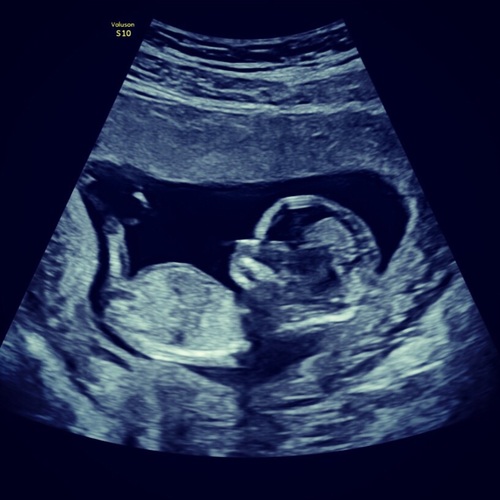

Ik heb het ook gehad..dacht zelf ruim 7 weken zwanger te zijn. Alleen een vruchtzak te zien. Ik moest er niet vanuit gaan dat het een week later wel goed zou zijn. Er werd een miskraam verwacht, ze begon al over pillen die ik misschien moest gaan inbrengen als het niet vanzelf kwam. En dat ik weer terug moest naar de fertiliteitsarts. Verbazing alom toen er een week later een kind met kloppend hart te zien was..inmiddels 19 weken zwanger!

Ik hoop en gun je hetzelfde!! Veel sterkte tijdens het wachten..

Ik wist niet wanneer ik zwanger was geworden (nog geen duidelijke cyclus na stoppen pil). Dacht minder ver te zijn dan de vk had berekend. Ook alleen een lege vruchtzak te zien, zou volgens de vk een miskraam worden, geen andere opties. 2 weken later naar de gyn omdat de ‘miskraam’ niet op gang kwam. Daar een kindje met kloppend hartje... eerste echo was gewoon te vroeg. Natuurlijk enorm blij, maar tot ongeveer 14 weken wel erg onzeker hier over geweest!

Inmiddels dat gevoel los gelaten en bijna 25 weken in verwachting van een meisje 👶🏼💗